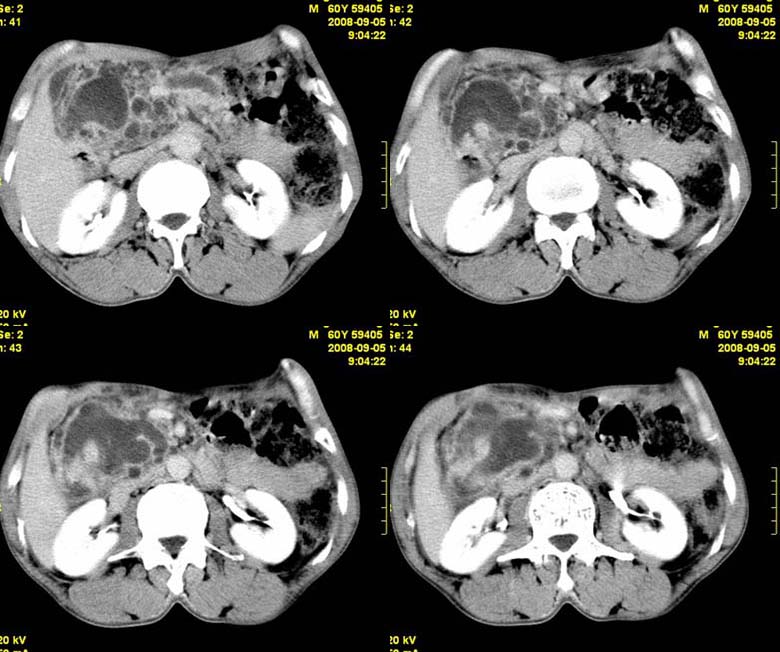

标题: CT15580:M60Y,胰腺病变,平扫+增强 [打印本页]

标题: CT15580:M60Y,胰腺病变,平扫+增强

患者,男, 60,既往有间歇腹痛病史多年,现右上腹痛,加重一月,伴右后背部疼痛,无黄疸,无发热。

考虑胰腺囊腺瘤或慢性胰腺炎

胰头区增大,胰管明显扩张,不均匀强化,且与 周围结构不清,后背疼痛,考虑为胰腺头部胰腺癌。

胰头囊腺癌

胰头囊腺癌

慢性胰腺炎

胰头囊腺癌

慢性胰腺炎并胰头癌

胰头囊腺癌。

胰腺囊腺瘤可能性大,囊腺癌不除外.

同意胰头部囊腺癌。

胰头囊腺癌可能性大。

考虑胰腺囊腺瘤或慢性胰腺炎

胰头囊腺癌

结合病史考虑慢性胰腺炎伴脓肿形成。

胰腺囊腺癌/慢性胰腺炎,建议查肿瘤标志物。

胰头囊腺瘤/囊腺癌.

胰腺炎,胰液滞留性假囊肿

考虑胰腺囊腺瘤或慢性胰腺炎。

胰头区增大,胰管明显扩张,不均匀强化,且与 周围结构不清,后背疼痛,考虑为胰腺头部胰腺癌。

胰头囊腺癌

考虑胰腺囊腺瘤或慢性胰腺炎可能性大

粘液性囊腺瘤

同意胰头部囊腺癌

胰头囊样增大不均匀强化,腺管扩张。结合病史首诊慢性胰腺炎、假性囊肿